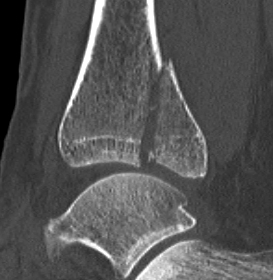

Mason and Malloy Classification

CT scan critical to classify and guide treatment / approach

| Type I | Type IIA | Type IIB | Type III |

|---|---|---|---|

| Avulsion of the PITFL |

Posterolateral fragment Volkmann fracture |

Posteromedial & posterolateral fragments Volkmann plus secondary fracture line |

Large coronal plane fragment Plafond fracture |